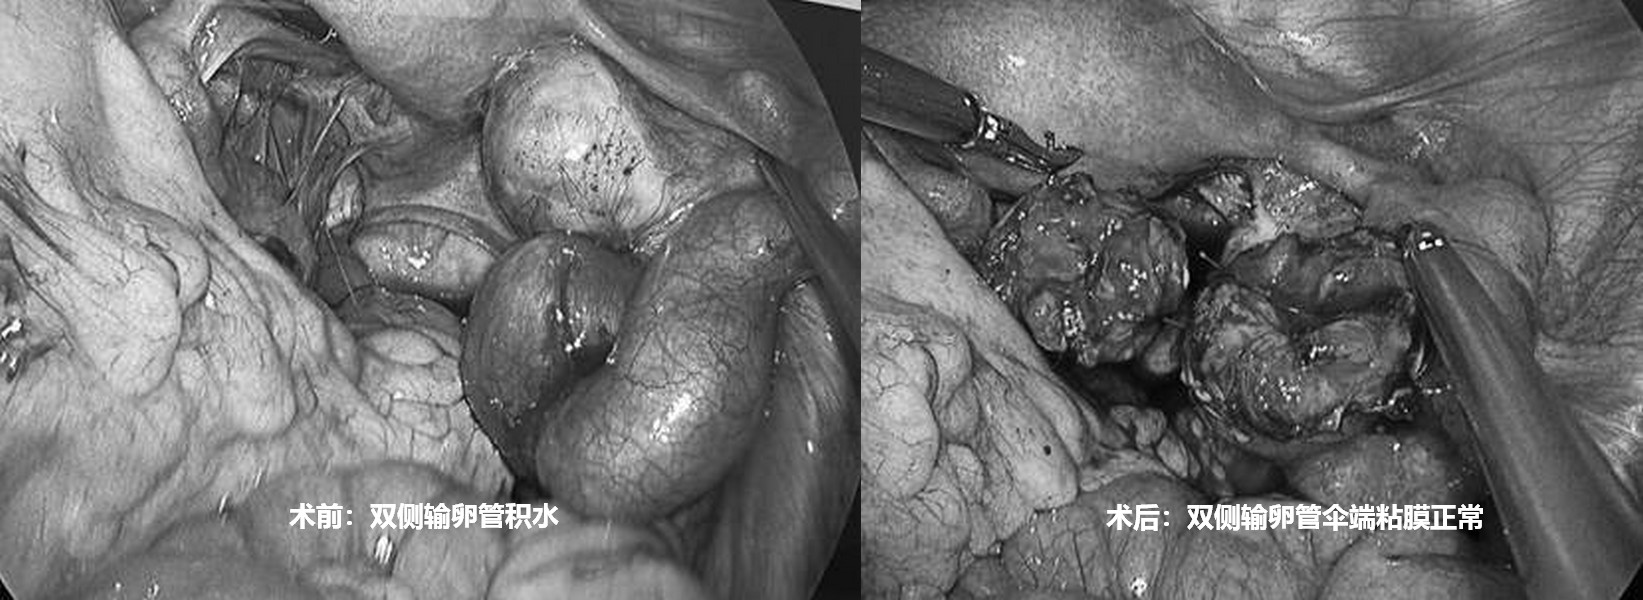

输卵管积水,想怀孕的最好方式是什么?